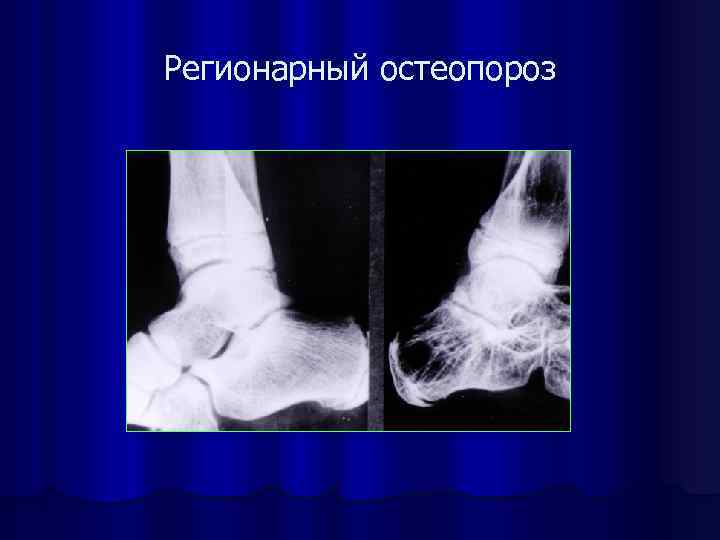

Регионарный остеопороз